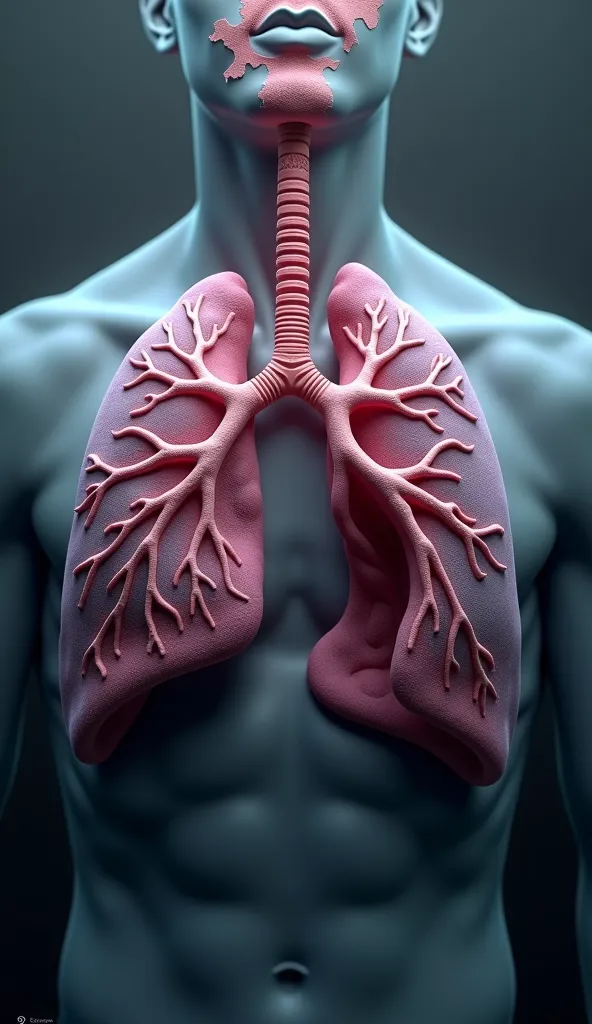

Make a folder about bacterial pneumonia

Make a folder about bacterial pneumonia